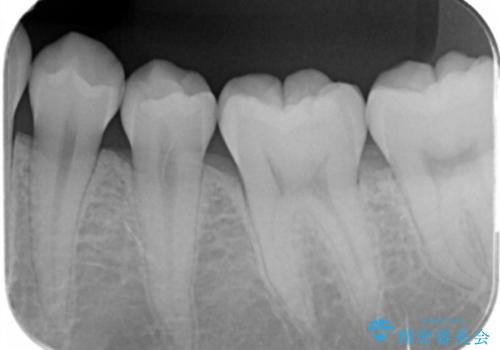

- 奥歯が黒いのが気になるとのことで来院。

レントゲンを確認したところ虫歯が大きくないので、以下の治療の提案を行った。

①虫歯を除去し、CR(レジン樹脂)で埋める。

安価で一日で終わり歯質を削る量が少ないが劣化しやすい(着色しやすい)。

虫歯の再発リスクが高い。

②虫歯を除去し、e-maxインレーで治療する。

歯質を削る量がCRで治療するより多く、また来院回数も多くなる(2回)。

劣化しにくく、虫歯の再発リスクが少ない。

コストがかかる。